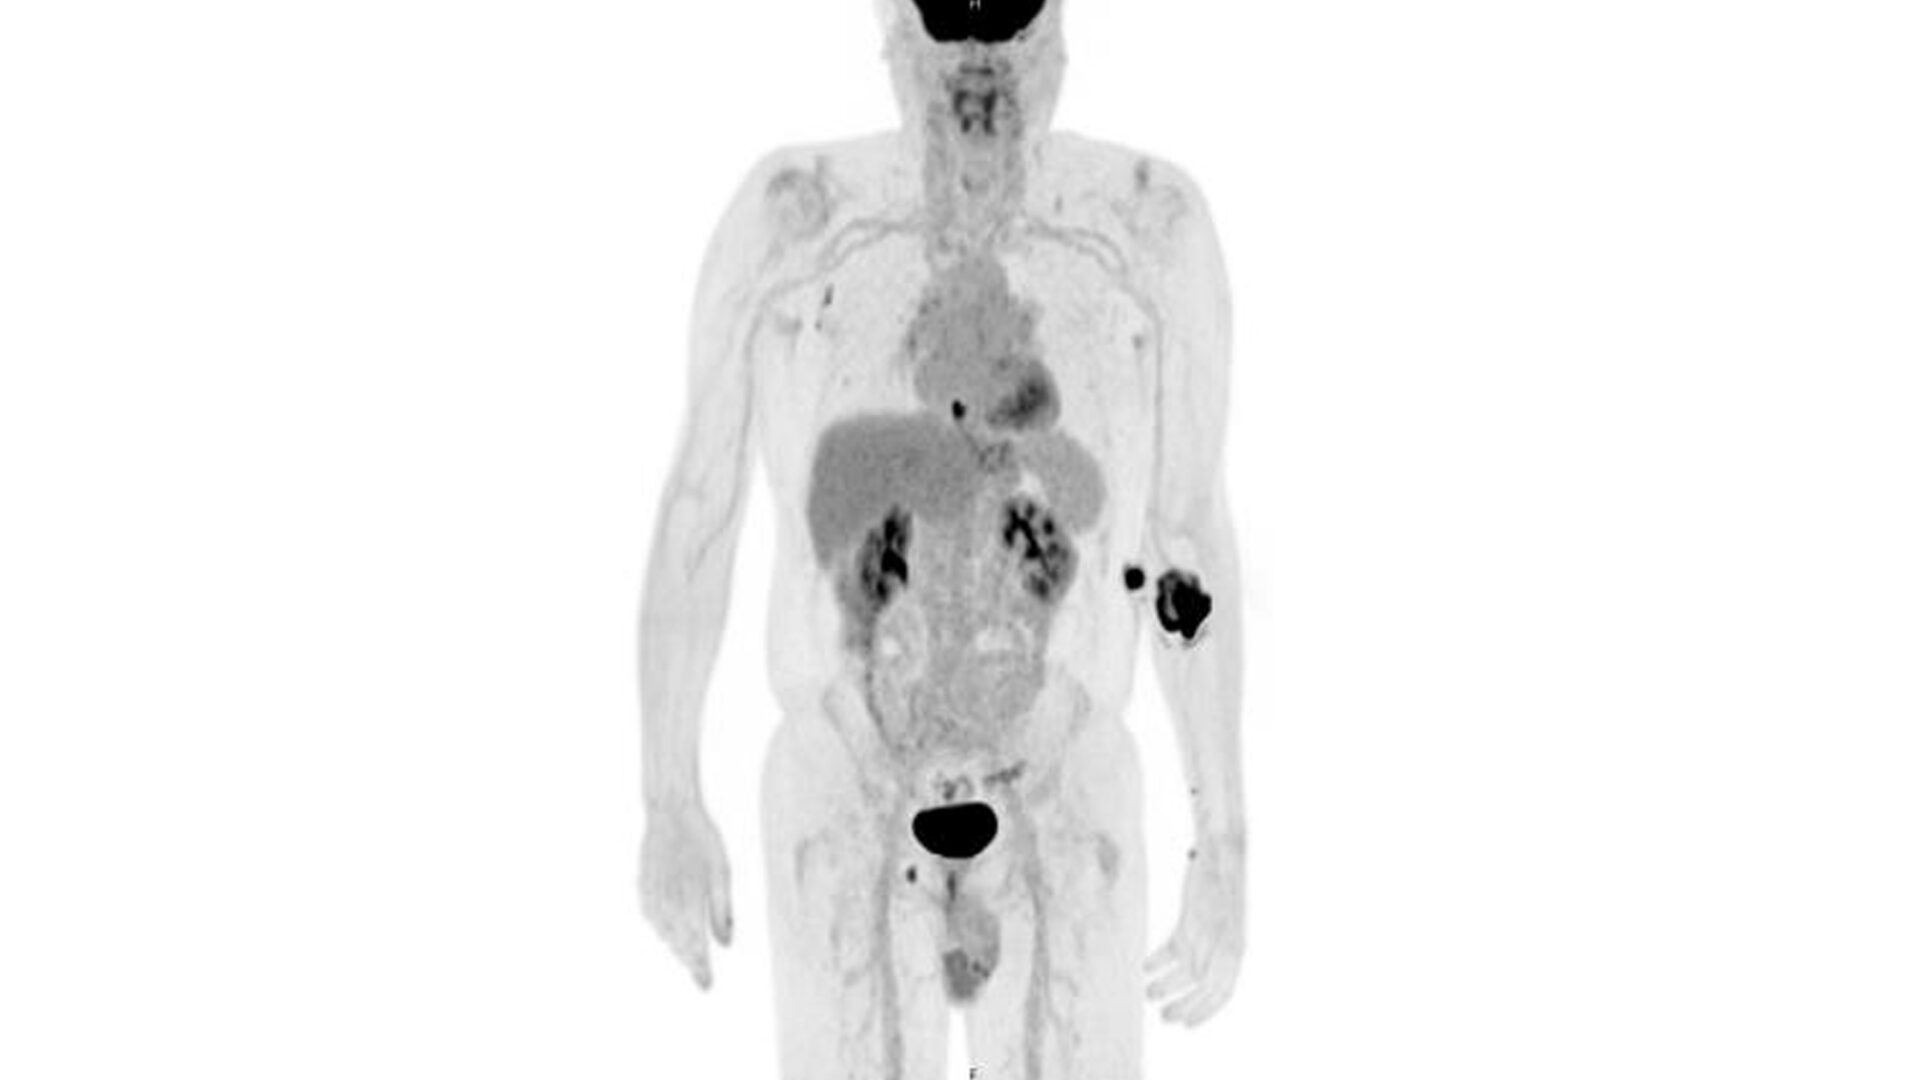

FDG Uptake

PET/CT showing FDG uptake at the distal esophagus, consistent with malignancy. There is also FDG uptake at the gastroesophageal junction, likely inflammatory or physiologic, along with FDG-avid bilateral hilar foci, right axillary nodes, and a right inguinal node—findings most consistent with inflammation. Source: NYU Langone Health